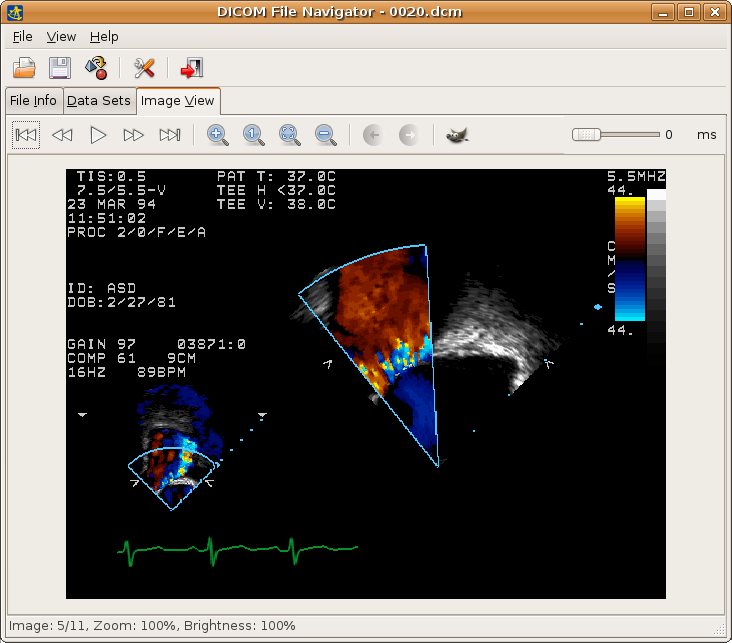

10. openDICOM.NET

openDICOM.NEt is a project that implements a completely new approach to DICOM libraries. It is written in C# and includes opendicom-utils for working with data dictionaries in different formats.

Its features include a tree view of ACR-NEMA and DICOM content, support of ACR-NEMA and DICOM images export to different image formats, image view with single and multiple frame support, image slide cycling known as movie mode, full DICOM 2007 data and UID dictionaries, etc.